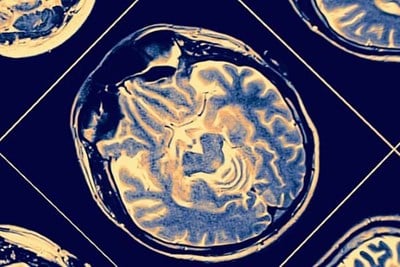

The focus of Dr. Miller's research career has been on improving the clinical care of newborns at high-risk of brain injury including newborns with congenital heart disease and those born preterm. The use of advanced brain imaging offers tremendous potential to understand the mechanisms and timing of brain injury in high-risk newborns and fetuses. Findings from his research program will ultimately inform the design and implementation of new strategies to promote optimal brain development and neurodevelopmental outcome. Dr. Miller uses multimodal magnetic resonance brain imaging (e.g. MRI, diffusion tensor imaging spectroscopic imaging) to study clinical factors associated with brain injury and neurodevelopmental outcomes among various fetal and neonatal populations (fetuses & newborns with congenital heart disease; babies born preterm). He is actively involved with numerous prospective, longitudinal studies including those with colleagues in Canada and internationally.